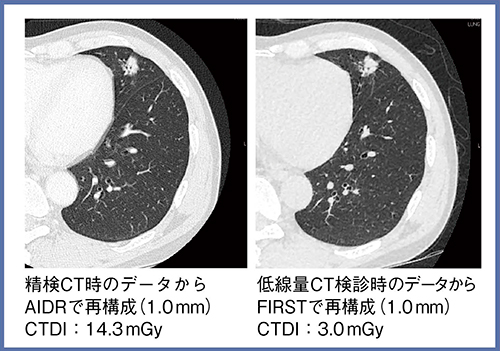

症例5(60歳代,男性)は,低線量CT検診で要精検となり,腺癌stage1Aと診断された(図6)。低線量CT検診データをFIRSTで再構成した画像と,精検時の通常線量CTのAIDR 3Dを比べると,空間分解能はほぼ同等であることがわかる。低線量CT検診は高ヘリカルピッチ(1.38)で撮影しているため,心臓のブレが少なく,通常線量CTよりもむしろ空間分解能が上がっている印象さえある。

症例6(60歳代,男性)では,MIP像による末梢血管の描出を,通常線量CTのAIDR 3Dと低線量CT検診のFIRSTで比較した(図7)。線量を約1/4に抑えても,FIRSTで再構成することで同等の空間分解能を得られることがわかる。

図6 症例5:肺腺癌stage1A(60歳代,男性)

図7 症例6:肺がん検診例(60歳代,男性)